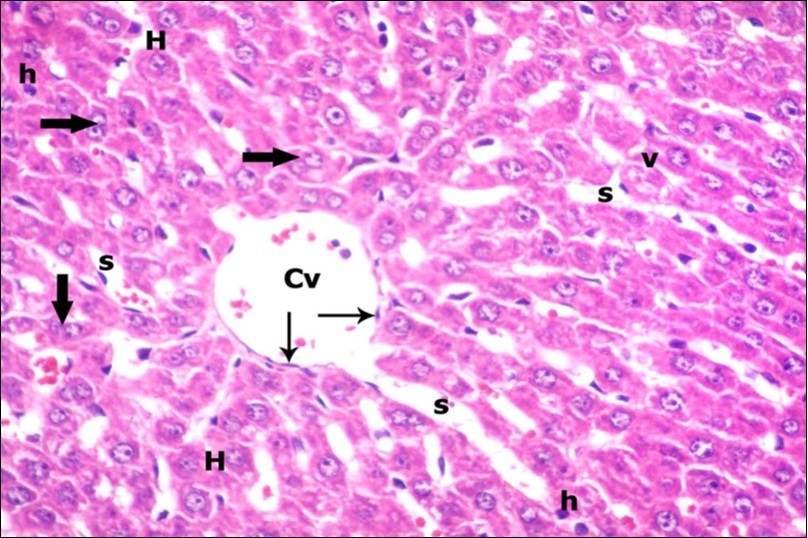

Examination of H&E stained sections of the 1st group (control group) revealed hepatic architecture of tightly packed cords of hepatocyte with vesicular nuclei and acidophilic cytoplasm radiating from the central vein (Figure 1). Portal area was composed of a portal vein, branch of hepatic artery and bile duct lined by single cuboidal cells with dark rounded nuclei. Blood sinusoids with their endothelial lining of Kuppfer cells were noticed in between hepatic cords (Figure 2). Examination of the liver sections of the 2nd group (vitamin E treated group) showed nearly the same histological features as the 1st group. The 3rd group (ZnONPs-treated group) showed a marked loss of the normal liver arrangement with dilated congested central veins and blood sinusoids. Most of hepatocytes had large cytoplasmic vacuoles and darkly stained nuclei other hepatocytes were ballooned (Figure 3). The portal area showed dilated congested portal vein with proliferation of bile duct, necrotic foci in between the hepatocytes with inflammatory cellular infiltration (Figure 4). The portal area showed also elongation of the endothelial lining of dilated congested portal vein and increasing amount of connective tissue fibers (Figure 5). There was congested hepatic artery with increasing thickness of its muscular layer (Figure 6). Bile duct showed proliferation with stratification of its epithelial lining (Figure 7).

Figure 1.A photomicrograph of a section in the liver of a control adult albino rat showing polygonal hepatocytes (H) radiating from central vein (Cv) with rounded vesicular nuclei and acidophilic cytoplasm. Narrow radiating blood sinusoids (s) in between liver cords and their lining endothelium are noticed. Binucleated cell is also seen (thick arrow). (H&E X400)